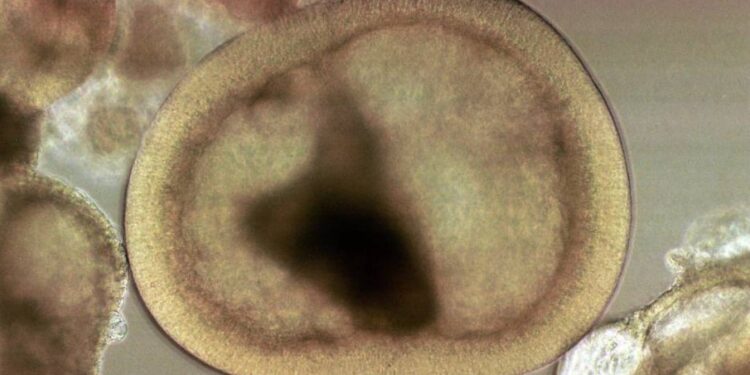

കോട്ടയം: ശരീരത്തിലെ പരിക്കുകൾ ഭേദമാക്കുന്നതിനും കോശ പുനരുജ്ജീവനത്തിനും സഹായകമാകുന്ന ജൈവ പോളിമർ ഉത്പന്നങ്ങൾ വികസിപ്പിച്ചെടുക്കുന്നതിന് ബ്രസീൽ, റഷ്യ, ഇന്ത്യ ചൈന, സൗത്ത് ആഫ്രിക്ക (ബ്രിക്സ്) എന്നീ രാജ്യങ്ങൾ ചേർന്ന് രൂപം കൊടുത്തിട്ടുള്ള ഗവേഷണ പദ്ധതിക്ക് നേതൃത്വം നൽകാൻ മഹാത്മാഗാന്ധി സർവകലാശാല.

നാനോ സെല്ലുലോസ് സാങ്കേതികവിദ്യ പ്രയോജനപ്പെടുത്തി ജൈവപോളിമർ ഉപയോഗിച്ച് ഇതിനാവശ്യമായ ഉത്പന്നങ്ങൾ നിർമിക്കുകയാണ് ലക്ഷ്യം. നാനോ, പോളിമർ ഗവേഷണത്തിൽ, വൈസ് ചാൻസലർ പ്രൊഫ. സാബു തോമസിന്റെ നേതൃത്വത്തിൽ മഹാത്മാഗാന്ധി സർവകലാശാല കൈവരിച്ച നേട്ടങ്ങളാണ് ഈ ഗവേഷണ പദ്ധതിക്ക് സർവകലാശാലയെ അർഹമാക്കിയത്.